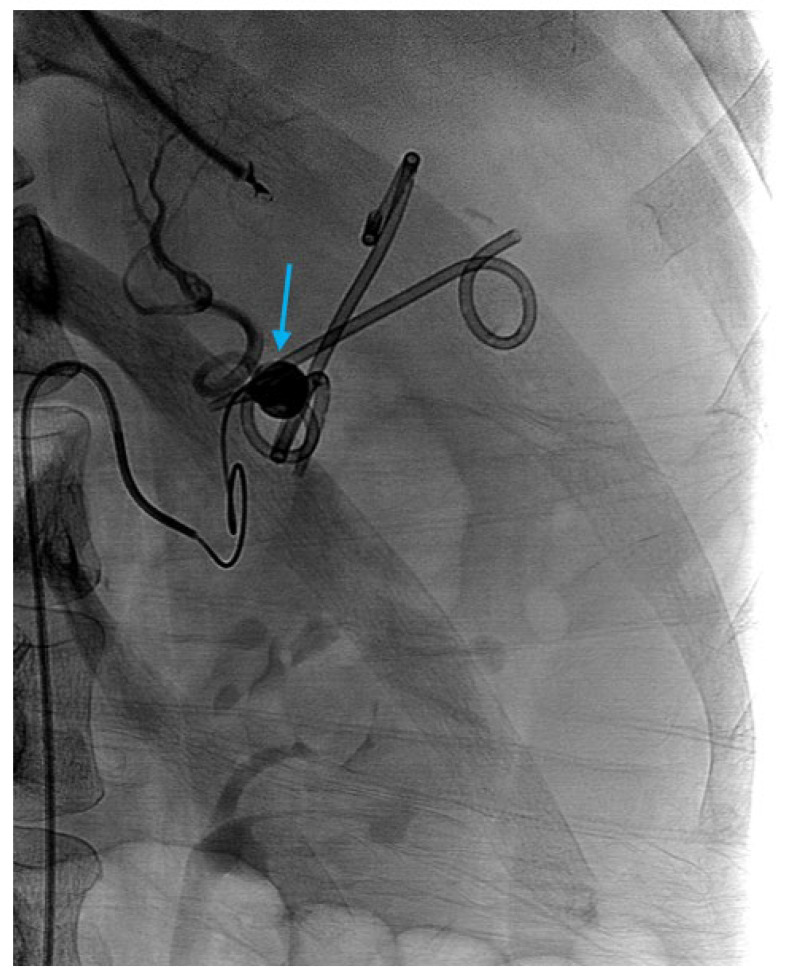

在美国,急性胰腺炎(AP)是胃肠道相关住院治疗的最常见原因,其中胆结石疾病和酒精是主要病因。治疗取决于疾病的严重程度,分为间质性水肿性胰腺炎或坏死性胰腺炎,严重程度根据局部并发症和全身器官功能障碍进一步分层。无论病因如何,初始治疗包括积极的乳酸林格氏液静脉液体复苏、疼痛和恶心控制、24至48小时内早期口服喂养,并在必要时进行病因指导干预。在胆源性胰腺炎中,当伴有胆管炎或持续性胆道梗阻时,早期内镜逆行胆管造影(ERCP)联合括约肌切开术,随后腹腔镜胆囊切除术作为结石清除的标准护理。在急性期,介入治疗在无并发症AP中的作用有限,除了胆道减压或鼻空肠管置入的肠内喂养支持。然而,在伴有并发症的严重AP中,介入放射学(IR)和内镜入路起着关键作用。IR有助于早期经皮引流有症状的急性积液和感染坏死,特别是在非内窥镜可及的腹膜后积液或依赖积液中,通过逐步入路改善结果。红外引导血管造影栓塞是出血并发症的首选方式,包括假性动脉瘤。在延迟期,壁闭塞性坏死(WON)和胰腺假性囊肿采用超声内镜(EUS)引导引流治疗,直接内镜下坏死切除术(DEN)用于感染坏死。双模引流(DMD),结合经皮和内镜引流,越来越多地用于广泛或复杂的集合,反映了胃肠病学和介入放射学之间的合作努力,类似于在进行视频辅助腹膜后清创(VARD)的机构中存在的IR和外科之间的合作。胰周积液可能瘘入邻近的结构,包括胃、小肠或结肠,需要经毛细血管支架置入,或不需要用镜外夹(OTSC)或缝合装置额外封闭肠道渗漏。此外,胰管断裂的内镜下处理与经毛细血管或经壁支架置入在胰管断裂综合征(DPDS)的病例中起着关键作用。各种介入技术(包括腹膜后、腹腔镜、开放手术和内镜引流)的比较结果强调了向微创入路的转变,降低了发病率和住院时间。内窥镜和介入放射引导技术的整合已经改变了AP并发症的管理,多学科合作对于获得最佳患者结果至关重要。

Acute pancreatitis (AP) is the most common cause of gastrointestinal-related hospitalizations in the United States, with gallstone disease and alcohol as the leading etiologies. Management is determined by disease severity, classified as interstitial edematous pancreatitis or necrotizing pancreatitis, with severity further stratified based on local complications and systemic organ dysfunction. Regardless of etiology, initial treatment involves aggressive intravenous fluid resuscitation with Lactated Ringer's solution, pain and nausea control, early oral feeding in 24 to 48 h, and etiology-directed interventions when indicated. In gallstone pancreatitis, early endoscopic retrograde cholangiopancreatography (ERCP) with sphincterotomy is indicated in the presence of concomitant cholangitis or persistent biliary obstruction, with subsequent laparoscopic cholecystectomy as standard of care for stone clearance. The role of interventional therapy in uncomplicated AP is limited in the acute phase, except for biliary decompression or enteral feeding support with nasojejunal tube placement. However, in severe AP with complications, interventional radiology (IR) and endoscopic approaches play a pivotal role. IR facilitates early percutaneous drainage of symptomatic, acute fluid collections and infected necrosis, particularly in non-endoscopically accessible retroperitoneal or dependent collections, improving outcomes with a step-up approach. IR-guided angiographic embolization is the preferred modality for hemorrhagic complications, including pseudoaneurysms. In the delayed phase, walled-off necrosis (WON) and pancreatic pseudocysts are managed with endoscopic ultrasound (EUS)-guided drainage, with direct endoscopic necrosectomy (DEN) reserved for infected necrosis. Dual-modality drainage (DMD), combining percutaneous and endoscopic drainage, is increasingly utilized in extensive or complex collections, reflecting a collaborative effort between gastroenterology and interventional radiology comparable to that which exists between IR and surgery in institutions that perform video assisted retroperitoneal debridement (VARD). Peripancreatic fluid collections may fistulize into adjacent structures, including the stomach, small intestine, or colon, requiring transpapillary stenting with or without additional closure of the gut leak with over-the-scope clips (OTSC) or suturing devices. Additionally, endoscopic management of pancreatic duct disruptions with transpapillary or transmural stenting plays a key role in cases of disconnected pancreatic duct syndrome (DPDS). Comparative outcomes across interventional techniques-including retroperitoneal, laparoscopic, open surgery, and endoscopic drainage-highlight a shift toward minimally invasive approaches, with decreased morbidity and reduced hospital stay. The integration of endoscopic and interventional radiology-guided techniques has transformed the management of AP complications and multidisciplinary collaboration is essential for optimal patient outcomes.